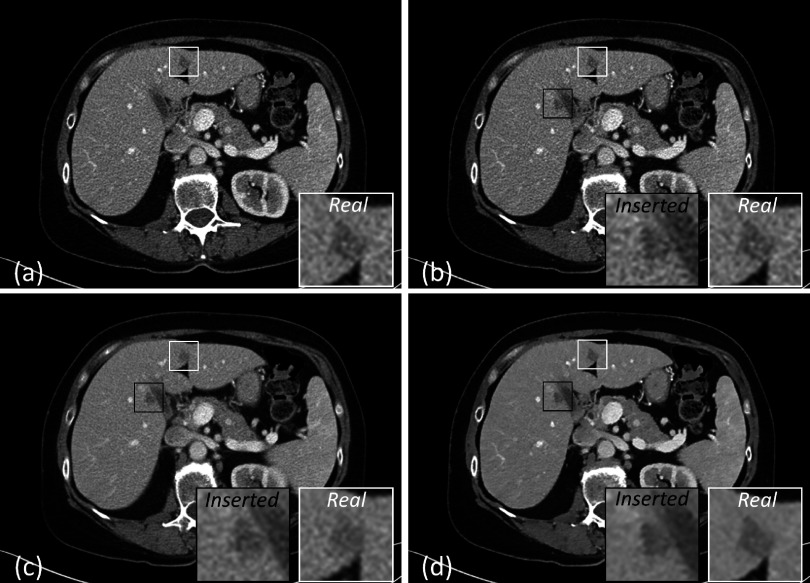

- 不同扫描条件下肝脏病灶的结果(全图+放大图)

- (a) The patient image reconstructed with a FBP B40f kernel and 2 mm slice thickness

- (b) The hybrid image reconstructed with a FBP B40f kernel and 2 mm slice thickness

- (c) The hybrid image reconstructed with a FBP B40f kernel and 5 mm slice thickness

- (d) The hybrid image reconstructed with a SAFIRE I40f kernel (strength of 5) and 2 mm slice thickness